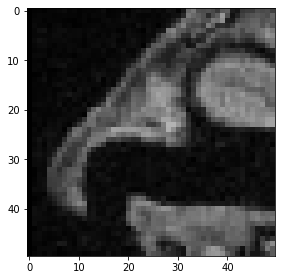

Pour visualiser des images 3D à l’aide de la fonction imshow de scikit-image, nous devons sélectionner une tranche à visualiser. Par exemple, une tranche Z :

slice_image = image[100]

imshow(slice_image)

../_images/b9ec53895c9942461dd35e1b88b95a9557441ceb09c074bd865d8bb6ddfdb74b.png